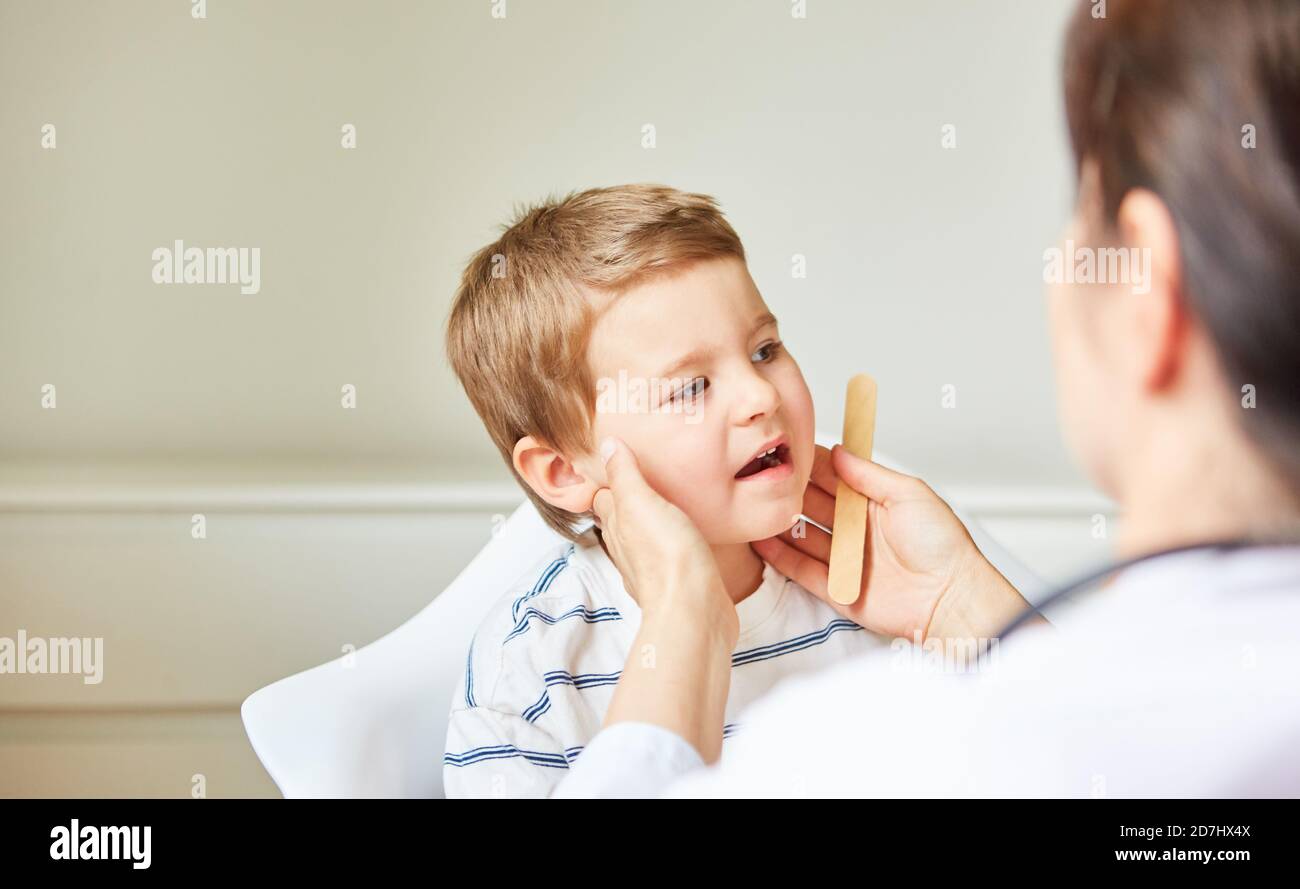

Kinderarzt palpates Mandeln und geschwollene Lymphknoten bei Kindern mit Tonsillitis Stockfotohttps://www.alamy.de/image-license-details/?v=1https://www.alamy.de/kinderarzt-palpates-mandeln-und-geschwollene-lymphknoten-bei-kindern-mit-tonsillitis-image383324394.html

Kinderarzt palpates Mandeln und geschwollene Lymphknoten bei Kindern mit Tonsillitis Stockfotohttps://www.alamy.de/image-license-details/?v=1https://www.alamy.de/kinderarzt-palpates-mandeln-und-geschwollene-lymphknoten-bei-kindern-mit-tonsillitis-image383324394.htmlRF2D7HX4X–Kinderarzt palpates Mandeln und geschwollene Lymphknoten bei Kindern mit Tonsillitis